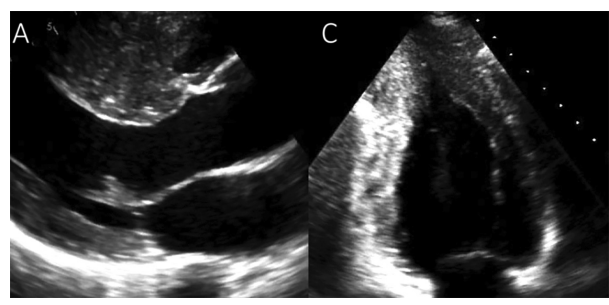

Analise o ecocardiograma a seguir.

Sendo esse exame a modalidade de escolha inicial para o diagnóstico dessa patologia, assinale a alternativa correta.